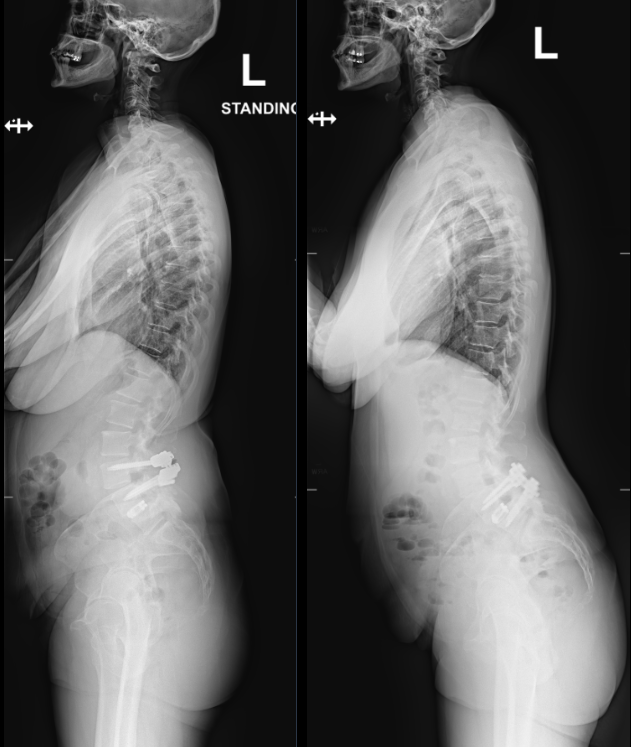

We are proud to announce that Dr. Brenton Pennicooke recently performed the very first TOPS (Total Posterior Spine) procedure within the BJC system by a WashU Medicine provider. The procedure, performed at Barnes-Jewish St. Peters Hospital, offers a motion-preserving alternative to traditional spinal fusion. This milestone represents an important step in expanding advanced spine care at WashU Medicine.

The TOPS implant works by stabilizing the spine after relieving pressure on the nerves while still allowing natural movement. Preserving motion at the treated level helps maintain normal spine mechanics and may reduce stress on adjacent segments, a common concern with fusion.

This approach can support faster recovery, improved function, and a lower risk of future complications. It offers meaningful improvement for patients with complex spinal conditions, broadening surgical options for those who need them most.